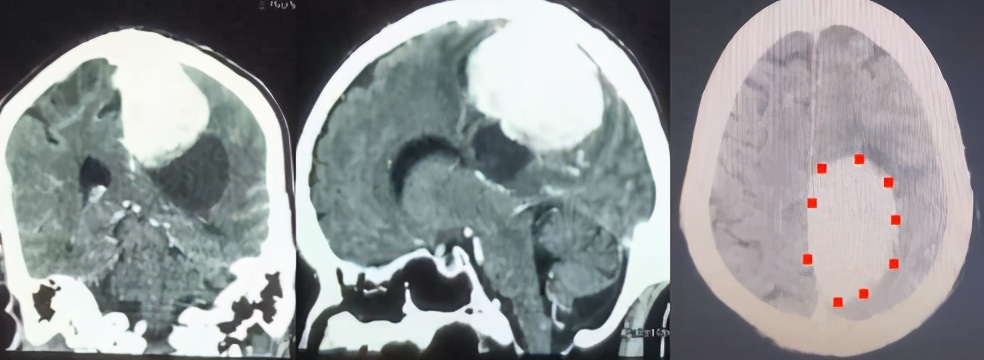

术前CT增强扫描影像(肿瘤位于大脑镰,累及矢状窦)

入院后完善检查,行头颅CT增强检查可见肿瘤位于左侧大脑镰部,并累及上矢状窦,且肿瘤深部还有一囊性病变,肿瘤强化明显,压迫运动区脑组织,造成患者右侧肢体瘫痪。患者年龄大,心肺功能不正常,并合并股骨颈骨折。为了保证手术的顺利进行,外科张强主任组织神经外科、麻醉科、心病科、肺病科、骨科等相关科室,进行会诊和术前讨论,制定了合理稳妥的手术治疗方案。